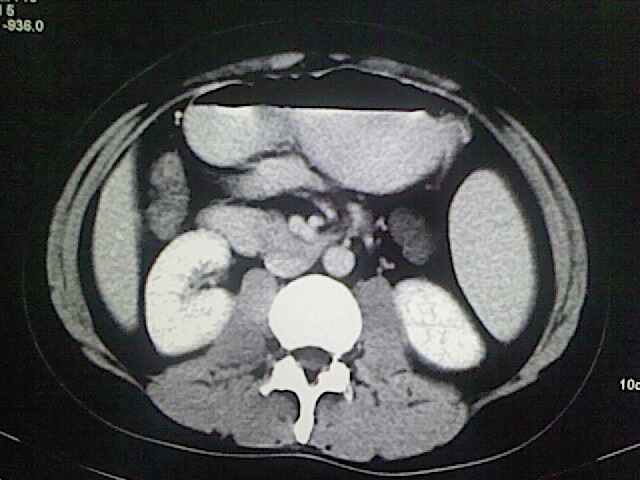

以下是引用卜一在2009-3-14 9:49:00的发言:[br]胆囊萎缩,胆囊壁不规则增厚,内部结构模糊,增强明显强化。另:肝左叶外侧段肝囊肿。支持:慢性胆囊炎!高度可疑:胆囊癌!

以下是引用余辉在2009-3-14 8:48:00的发言:[br]1)慢性胆囊炎。2)肝左叶外侧段肝囊肿。3)脂肪肝。[br]支持,胆囊萎缩,密度增高,不知b超具体有何提示,钙胆汁?结石?

以下是引用jiangjing在2009-3-14 10:18:00的发言:[br]1)慢性胆囊炎。2)肝左叶外侧段肝囊肿。3)脂肪肝。4.】建议行肝功能检查